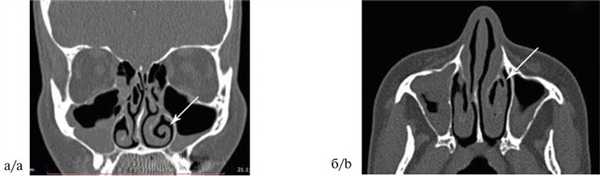

Эндоскопическое исследование носа: искривление перегородки носа вправо, резко выраженное увеличение левой ННР, незначительный эффект от аппликации деконгестантов. На спиральной КТ (СКТ) определяются воздушная полость (conhae bullosae) средней носовой раковины справа и патологический изгиб ННР, более выраженный слева (рис. 1). На основании результатов обследования выставлен диагноз: искривление перегородки носа, хронический гипертрофический ринит, патологический изгиб левой ННР. 14 марта 2017 г. были проведены одноэтапная септопластика, двусторонняя нижняя конхотомия, эндоназальное вскрытие верхнечелюстных пазух. Учитывая характер изгиба левой ННР, после редрессации была выполнена резекция ее подвернутого свободного края. Послеоперационный период протекал без осложнений. Больная выписана в удовлетворительном состоянии 18 марта 2017 г. При контрольном осмотре 17 апреля 2017 г. отмечено восстановление носового дыхания.

Рис. 1. Больная Ш., 42 года. Компьютерная томограмма околоносовых пазух: коронарная (а) и аксиальная (б) проекции. Патологический изгиб левой ННР (указано стрелками). Fig. 1. Patient Sh., aged 42 years. CT of the paranasal sinuses in the coronal (a)and axial (b) projections. The pathological bending of the left inferior nasal turbinated bone (shown by arrows).